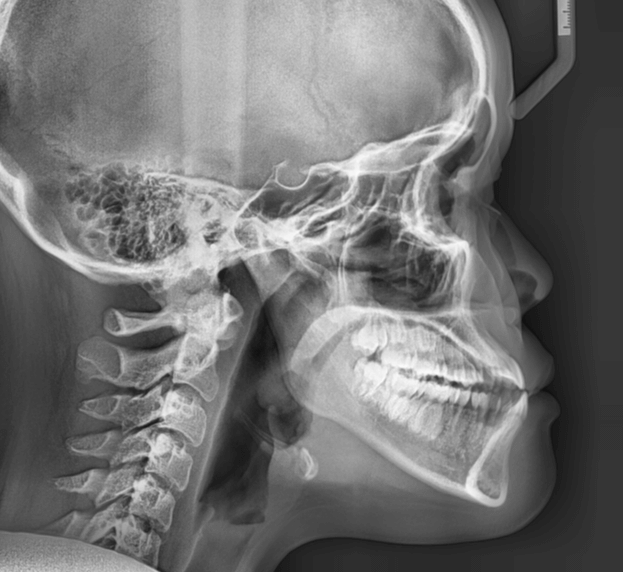

| 年齢・性別 | 15歳の女性 |

|---|---|

| 主訴 | 咬み合わせが逆であること(反対咬合)を気にされて来院された15歳7か月の女性。見た目や機能面の改善を希望されていました。 |

| 治療期間・回数 | 4年4ヶ月・28回 |

| 費用 | 900,000円 |